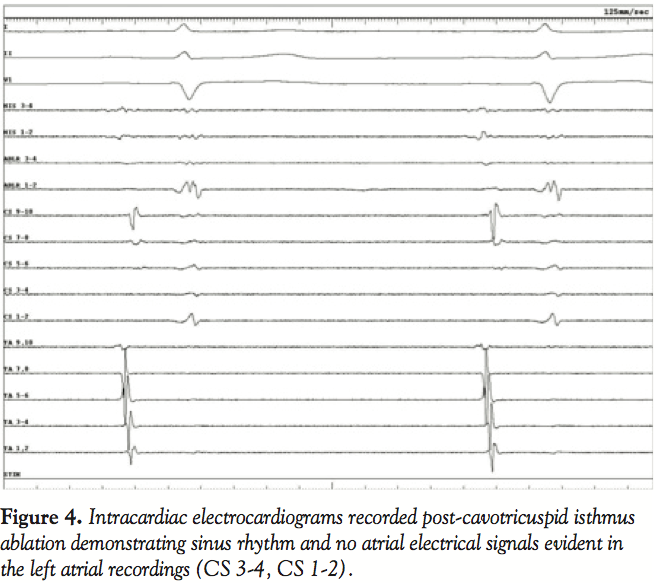

Diagnostic Evaluation. The patient was admitted for electrophysiologic study with multipolar catheters placed near the His bundle, in the coronary sinus, and around the tricuspid annulus. Analysis of the recordings demonstrated evidence of cavotricuspid isthmus (CTI)-dependent reverse typical atrial flutter rotating in the right atrium in a clockwise, caudocranial direction (Figure 3). However, coronary sinus recordings from electrodes reflecting left atrial activity (CS 3-4, CS 1-2) were electrically silent, compatible with atrial dissociation (Figure 3).

Presumably this finding was a result of the extensive ablation procedures the patient had undergone, creating interatrial conduction block, which resulted in the absence of electrical activity in the left atrium. This explained the presence of low amplitude atrial activity evident in the surface recordings despite the presence of sinus rhythm and then reverse typical atrial flutter, occurring in only the right atrial chamber. The 2 non-sinus rhythm ECGs were manifestations of atrial flutter with 2:1 AV conduction with and without bundle branch block with the flutter rate slowed by prior ablations and amiodarone therapy. Neither a sawtooth nor a sinusoidal ECG pattern was present, but careful scrutiny of lead II in both tracings did reveal low amplitude atrial activity compatible with this diagnosis. Radiofrequency ablation of the CTI resulted in bidirectional conduction block and restoration of sinus rhythm. Despite conversion, the left atrium recordings remained electrically silent (CS 3-4, CS 1-2) (Figure 4). The patient was discharged in stable condition and remained asymptomatic. Ultrasonography performed 3 months post-CTI ablation with pulsed Doppler examination of the mitral valve inflow demonstrated the absence of an “a” wave during diastolic filling despite continued maintenance of sinus rhythm compatible with atrial dissociation and absence of electromechanical activity in the left atrium. Anticoagulation therapy was continued indefinitely due to this finding.

The presented case was similar to these recent reports in that the patient had previously undergone extensive ablative and surgical procedures in an attempt to cure AF. Low amplitude P waves were present in the discharge ECG and then with the advent of the patient’s rhythm disturbance, atrial activity was not clearly apparent in the surface tracings. The electrophysiologic and echocardiographic data suggest that complete biatrial dissociation was present as a result of these procedures. Considering the anatomic relationships of the atria, the surface ECG in general reflects more left atrial activity than right and when the left atrium is electrically silent, ECG evidence of atrial activity is blunted. A subsequent invasive study documented the presence of CTI-dependent reverse typical atrial flutter localized only to the right atrium and this rhythm was treated with standard ablative approach. Intracardiac recordings reflecting left atrium remained electrically silent, which persisted late post-procedure, as no mechanical atrial function was evident 3 months post-procedure.